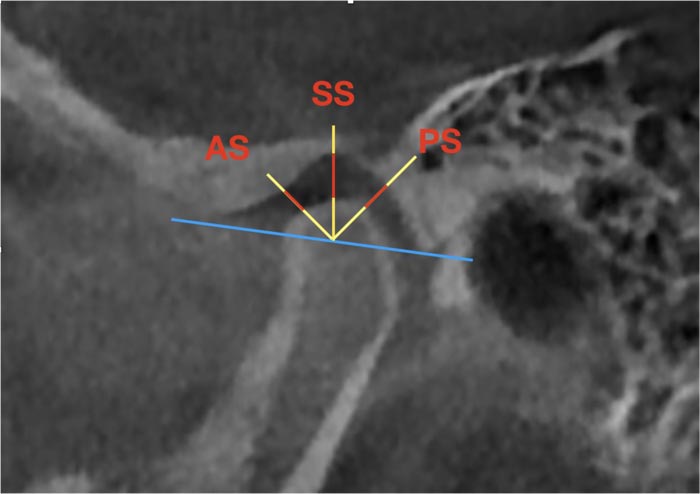

The articular space was also assessed on the sagittal reformat according to the following algorithm (Fig. 3):

(1) A line is drawn from the top of the articular tubercle to the petrotympanic fissure;

(2) A perpendicular is drawn from the center of the articular head to the above line, then the bisectors of the obtained right angles are built.

(3) Measurements of the anterior, superior, and posterior spaces were carried out along three corresponding lines in the area of the joint space.